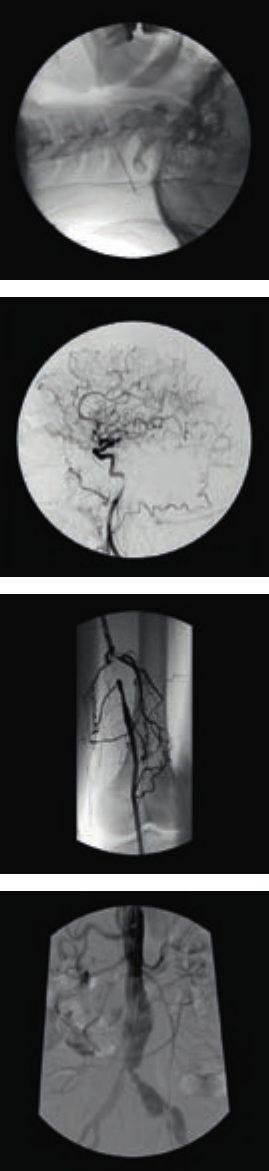

Vascular image

The Vascular Package, which includes subtraction,

can easily be combined with Extended Processing

functionssuchasZoomandMeasure.

Choose either a 9”or 12” triple-mode image intensifier, to match

your applicational requirements

The Vascular Package, which includes subtraction, can easily

be combined with Extended Processing functions such as

Zoom and Measure